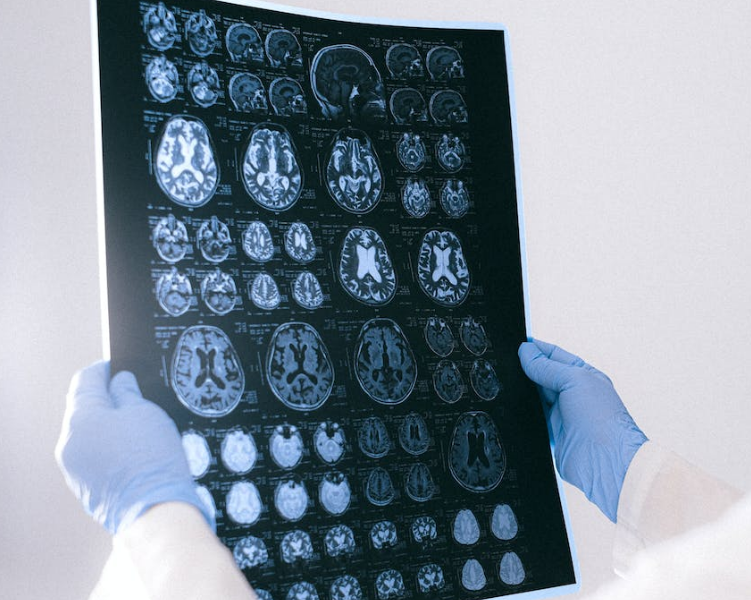

뇌는 우리 몸의 제어 중심이자 가장 중요한 기관 중 하나입니다. 그러나 때로는 다양한 위험으로 인해 뇌 세포가 손상을 입을 수 있습니다. 뇌 세포의 손상은 충격의 정도, 유형, 뇌 상태, 그리고 개인적인 요인에 따라 다양하게 나타납니다. 이 블로그 글에서는 뇌 세포의 손상과 관련된 주요 요소들을 자세히 살펴보고, 어떻게 뇌 손상을 예방하고 치료하는 방법에 대해 알아보겠습니다.

충격의 세기가 뇌 세포에 미치는 영향은 상당히 중요합니다. 강력한 충격은 뇌 세포에 상당한 손상을 입힐 수 있으며 이러한 충격은 교통사고나 폭발과 같은 상황에서 발생할 수 있습니다. 이러한 상황에서는 뇌 세포의 손상을 예방하기 위해 안전한 조치를 취하고 안전장비를 착용해야 합니다. 더 구체적으로, 교통사고 예방을 위해 안전벨트 착용과 안전 운전 습관을 유지하는 것이 중요합니다. 또한, 폭발이 발생할 가능성이 있는 환경에서는 안전 절차를 준수하는 것이 중요합니다.

충격이 뇌의 특정 부분에 영향을 미치면 그 부위와 관련된 뇌 세포의 기능에 영향을 줄 수 있습니다. 뇌는 여러 부분으로 구성되어 있으며 각 부분은 특정한 기능을 수행합니다. 따라서 특정 부위에 손상이 발생하면 그 부위와 관련된 기능에 문제가 발생할 수 있습니다. 이를 예방하기 위해 강력한 충격을 피하고 안전한 환경을 조성하는 것이 중요합니다.

충격이 얼마나 오래 지속되는지도 중요한 역할을 합니다. 긴 시간 동안 지속되는 충격은 뇌 세포에 더 큰 손상을 입힐 수 있으며, 이는 뇌 건강에 부정적인 영향을 미칠 수 있습니다. 따라서 위험한 상황에서는 빠르게 대응하고 충격 지속 시간을 최소화하는 것이 중요합니다. 충격이 지속되는 동안 안전한 위치로 이동하거나 구호 요청을 하여 도움을 받는 것이 중요합니다.

뇌 세포의 손상을 피하고 뇌 건강을 지키기 위해서는 안전을 최우선으로 고려해야 합니다. 안전장비를 착용하고 위험한 상황에서는 예방 조치를 취해야 합니다. 또한 뇌 손상의 초기 징후가 나타날 경우 즉각적인 의료 진료가 필요하며, 이러한 예방과 신속한 치료 조치는 뇌 세포 손상을 최소화하는 데 도움이 됩니다.